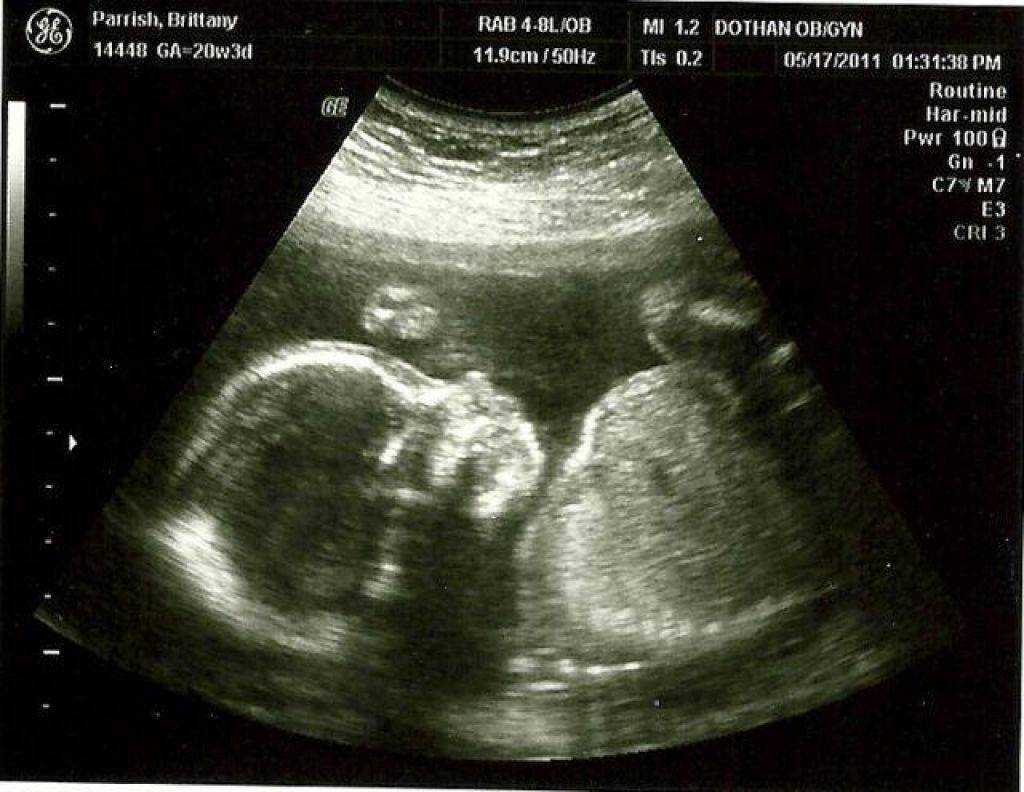

Если УЗИ проводится на 29 неделе беременности, четко видна половая принадлежность малыша. У мальчиков на этом сроке продолжается опускание яичек в мошонку. У девочек клитор немного выдается, так как он еще не прикрыт малыми половыми губами.

В период развития беременности 29 недель наступает время, когда у малыша можно услышать биение сердечка. Также можно тщательно рассмотреть и прослушать работу внутренних органов ребенка, на этом сроке он уже достаточно крупный для этого. Вес малыша на двадцать девятой неделе беременности должен составлять не менее 1200 граммов, а длина тела может превышать 35 сантиметров.

Щечки постепенно округляются вместе с другими частями тела. Так как половые органы сформировались достаточно хорошо, на УЗИ можно уже безошибочно определить пол малыша. С каждым днем организм ребенка начинает функционировать все лучше, превращаясь в гармоничную отлаженную систему. Связки и мышцы продолжают совершенствоваться и крепчать, что ощущается по силе толчков. Учитывая то, что места для кувырканий становится намного меньше, каждый переворот с головы на ноги и наоборот будет четко ощущаться мамочкой.